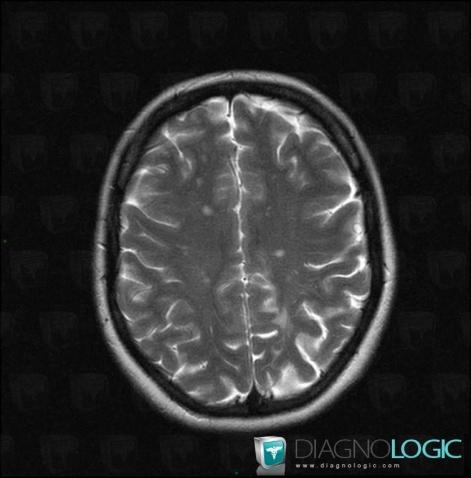

Multiple sclerosis, Cerebral hemispheres, MRI

Here is the specific information in the key image above:

- Diagnosis Multiple sclerosis, Location(s) Cerebral hemispheres, with gamuts Multifocal intracranial lesions, White matter disease, Intracerebral T2W or FLAIR hyperintense lesion